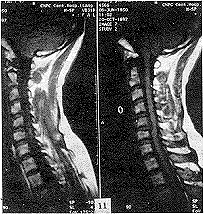

(3)顱骨:病變主要在顱底,尤其是蝶骨體及大、小翼改變明顯。蝶鞍大小正常,但鞍底、鞍背及前後床突皆增厚、變硬。枕骨及顳骨亦有明顯硬化。視神經孔變窄且邊緣模糊,乳突氣泡及副鼻竇腔均小或不發育。

重症石骨症容易診斷,輕型者有時診斷困難確診有賴於放射學檢查及家族史。對於有視神經萎縮者清晰的視神經管斷層攝片或採用冠狀加矢狀CT掃描,則能清楚地顯示病變的部位及程度石骨症的診斷依據為:

4.X線顱骨平片 顯示顱骨異常緻密及增厚,內外板及板障合為一體,難以分辨。顱骨高度鈣化密度顯著增高,顱窩變淺,垂體窩變小,額竇縮小,鞍背增生等。

X線表現:基本X線表現廣泛均勻,骨密度增高硬化,骨小梁變粗、模糊,皮質增厚,髓腔狹窄,甚至消失。本院曾有3例石骨症病人,因發生骨折,欲行帶鎖髓內針固定,因髓腔消失,骨質硬化,改用鋼板或動力髁鋼板固定,骨密度增高有明顯的均勻對稱性,以四肢、肋骨和骨盆較明顯。骨中骨主要見於掌指、跖趾關節及肋骨等,骨中骨表現為邊界比較明顯的緻密骨島。夾心椎又名夾心蛋糕征,其形成是由於椎體上下軟骨板富含血管,在鈣吸收不足的情況,該部類骨質沉積過多。類骨質對破骨細胞具有明顯的抑制作用,而椎體中部缺乏這種類骨質,故而被破骨細胞侵蝕,形成椎上下高密度而中間低密度,形如三明治樣。髂骨翼年輪樣改變。射線可透過帶是較正常骨區域,而緻密帶存在大量不起作用的破骨細胞。顱骨穹窿顱底均增厚硬化,以顱底骨質增生最明顯。

石骨症為全身性骨骼受累的疾病,顱骨的X線表現為硬化,尤以顱底為顯著,特別是蝶骨體及大、小翼均明顯改變。蝶鞍大小正常或縮小,床突、鞍底皆硬化。顳骨及枕骨也可硬化,使板障封閉,失去三層的分野。頂骨額骨及顏面骨可不受侵犯或僅有輕微變化。視神經孔變窄且邊緣模糊乳突小房及鼻旁竇變小或發育不全石骨症在長管狀骨及脊椎有特徵性的X線改變。脊椎椎體表現為上下緣特别致密,其間密度低者為正常骨質,組成三層帶狀影。長管狀骨表現為“骨內骨”,骨質緻密髓腔變窄或消失於乾骺部顯示多條互為平行或呈波狀緻密線紋,乾骺部可呈杵狀變形,尤其脛骨上端內側可表現為邊緣不整呈粗鋸齒改變,髂骨翼典型改變為平行髂嵴,的多層的同心弧狀硬化帶此外,肋骨和鎖骨均可呈均勻硬化。有時還可見到骨折,於掌、蹠、指及趾骨常有界限分明的骨島出現。